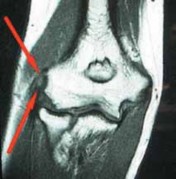

One study reports an incidence of calcification about the ECRB origin from chronic tendinosis in up to 25% of patients ( FIG 1A).9

Historically, magnetic resonance imaging (MRI) has had limited utility in the diagnosis of LE.

MRI can demonstrate ECRB tendon thickening, increased signal on T1 and T2 images, and in advanced disease high T2-signal cystic areas that correspond to partial or complete ECRB avulsions or large areas of mucoid degeneration, which are nonspecific findings for LE ( FIG 1B).

Despite its limited specificity for LE, MRI can be a useful, noninvasive technique to visualize concomitant intra-articular elbow pathology and soft tissue pathology.

- ### FIG 1 • A. Standard AP radiograph of the elbow showing calcification of the extensor carpi radialis brevis (ECRB) tendon.

- B. T1-weighted MRI of the elbow. Arrows show intermediate or high signal intensity of the ECRB tendon at its insertion site on the lateral epicondylitis.